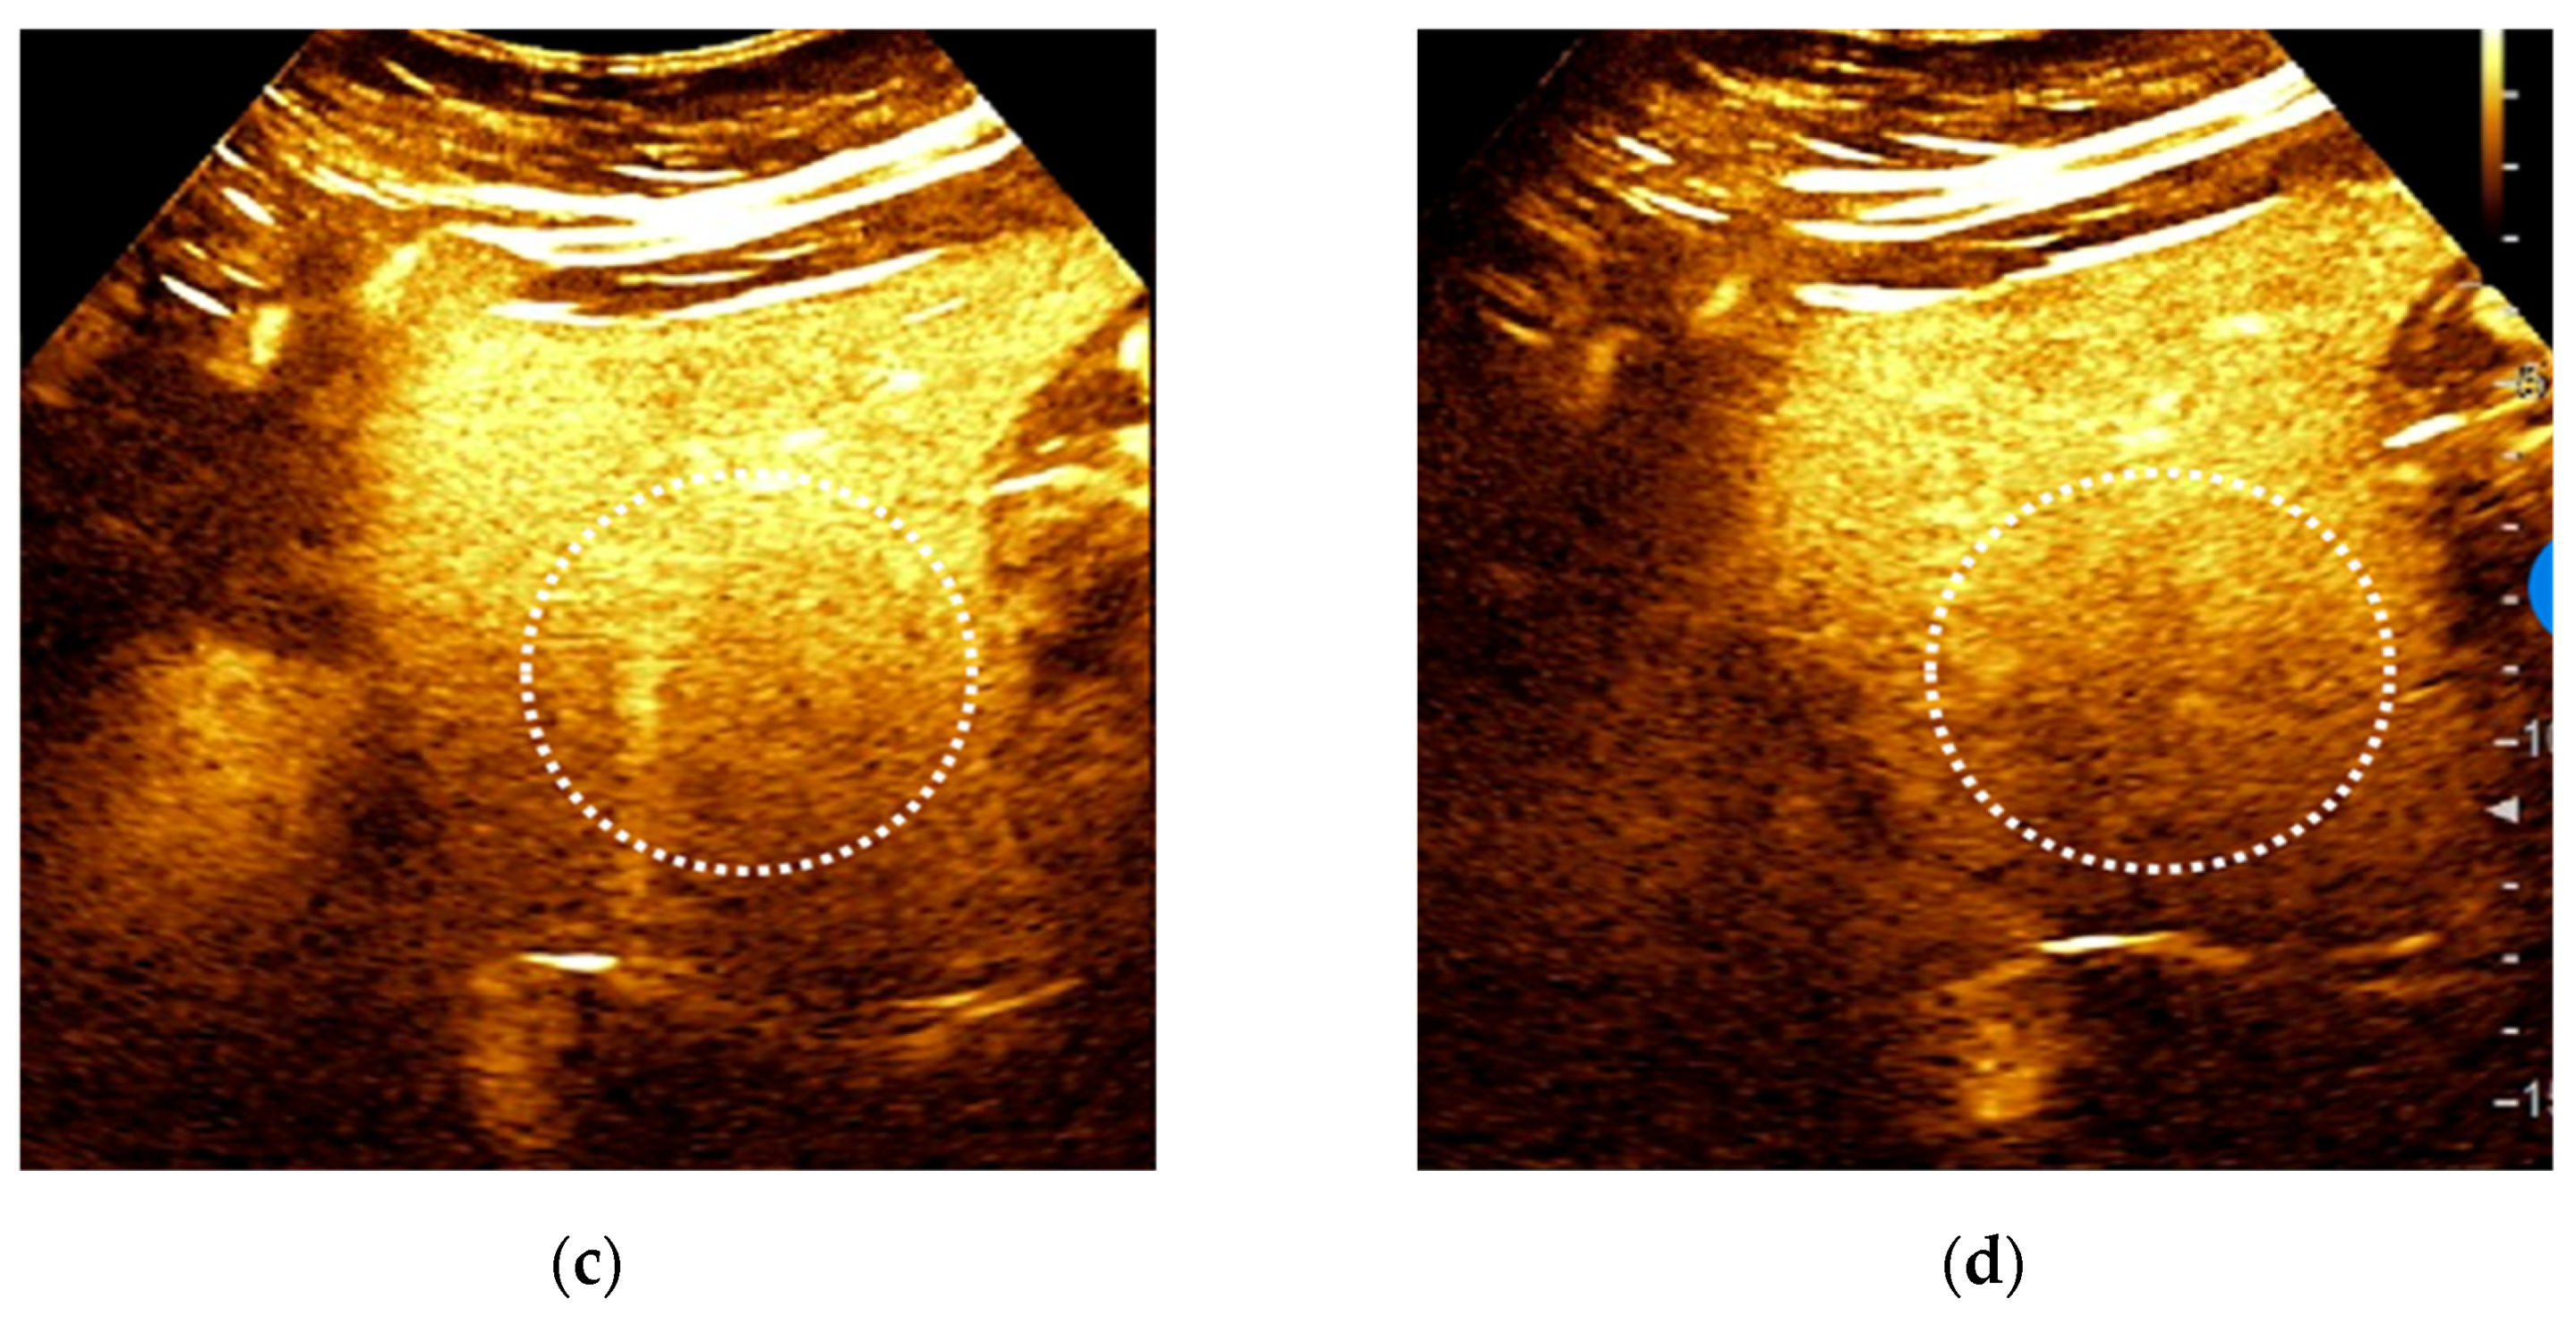

3.1. CEUS

3.1.1. CEUS Patterns According to LI-RADS Recommendations